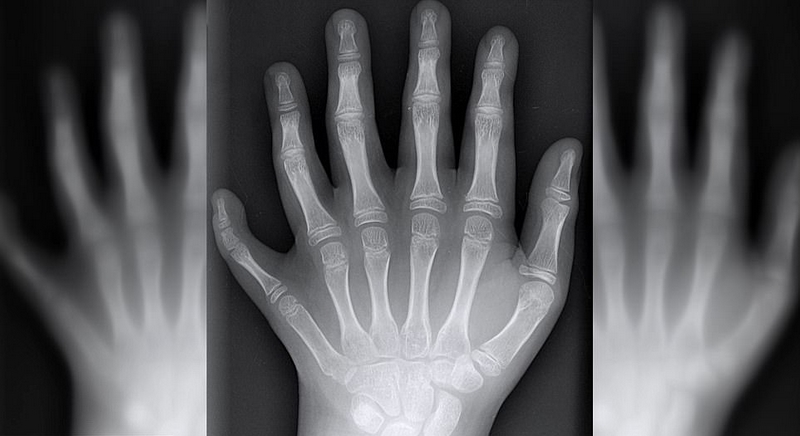

畸形对于大多数家庭而言都是噩耗。然而达席尔瓦家族却将其家族遗传的六指视若珍宝。23位家庭成员中共有14位患有多指畸形,他们的手指和脚趾都比常人多出2根。

一般来说,大部分多指畸形的患者无法使用他们多出来的手指,可是达席尔瓦家族的多指却可以正常使用。于是这种畸形非但没有成为阻碍,反而被认为是上天赐予的财富,他们可以利用多指的优势在音乐和足球等方面独占鳌头。譬如新生儿的哥哥乔阿西斯(Joao Assis),他是一名守门员。他说,六指可以让他在抓球时有更多着力点,所以球很难从他手里逃脱。